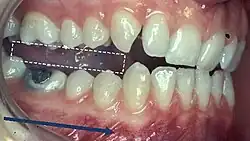

5) Contacts in ICP

Begin by assessing the incisor and molar relationship as described above. Similarly examine the overbite and overjet. An overbite of 3-5mm[2] and an overjet of 2-3mms are considered to be within the range of normal.[13]

To look at the ICP, articulating paper should be placed on the occlusal surface and the patient asked to bite together, which will mark their occlusal contacts. It is best to check these whilst the teeth are dry.

- During ICP, most opposing teeth should be contacting[2]

- Close examination of these contacts marked by the articulating paper help to identify the nature of the tooth contacts

- Good stable contacts often appear as small and not very prominent markings when articulating paper is used and there are multiple contacts on each tooth

- Broad and rubbing contacts identified in ICP may be associated with disturbances in function and may indicate occlusal instability[25]

- These contacts can be verified using Shimstock (a 12.5μm thick mylar strip) and the stability of the contacts can be checked